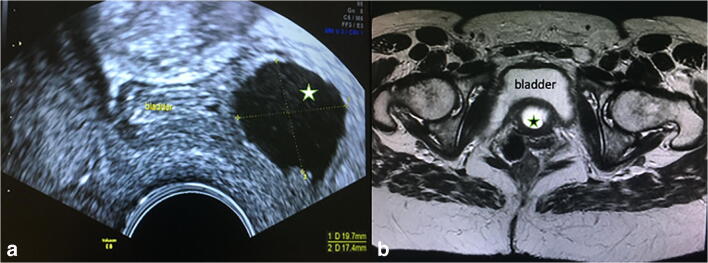

Fig. 3.

Magnetic resonance image at the level of the bladder above the urethra. The star demonstrates the fluid of the diverticulum